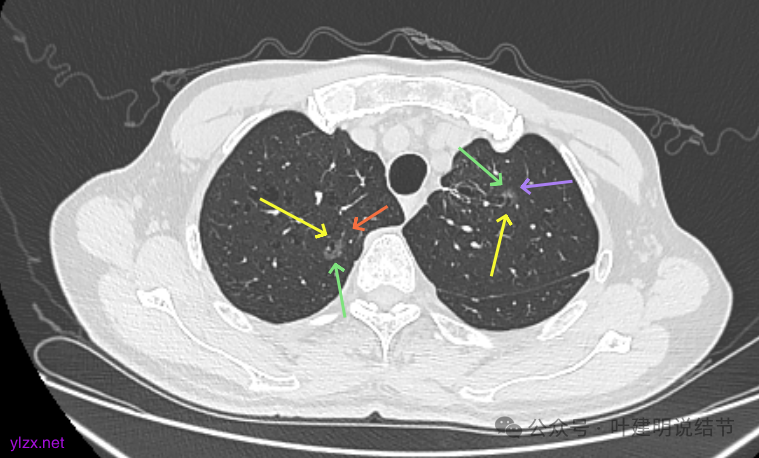

再看2022年9月的:

右上病灶此层面偏长条,密度较低。

左上已经手术。

左上另有一处磨玻璃结节,由于手术后结构变化,此灶是术前哪处感觉不太好对比。

再看2024年9月复查的:

右上的仍小而淡,轮廓仍是清楚的。

左上的病灶略显模糊,密度不太纯,较前相仿。

再看2024年9月的:

右上的较前略增大,且有空泡征较豙明显些,肿瘤的成分仍是纯磨密度。

左上病灶也是较为纯的,边缘不光滑,大小似乎略大一点点,不太显著。